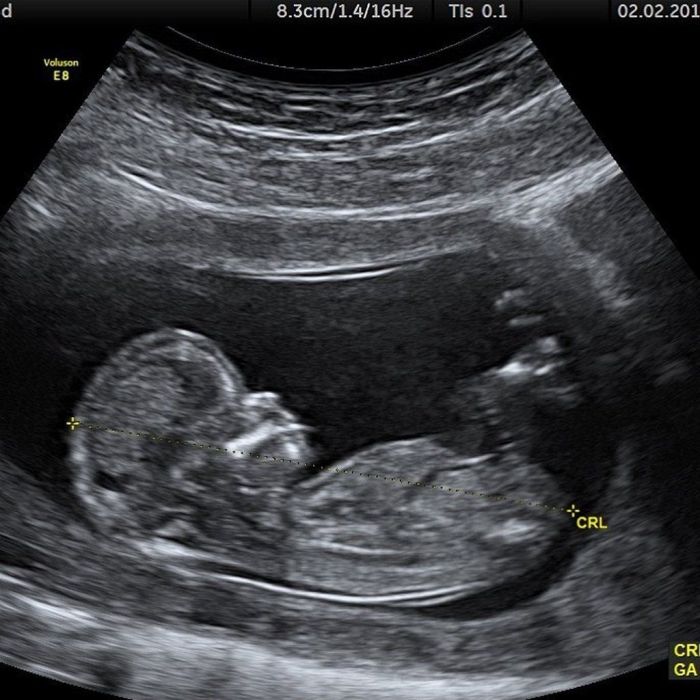

Πριν μερικές ώρες ο νεαρός τραγουδιστής ανέβασε στο Instagram account του μία φωτογραφία με ένα υπερηχογράφημα, αφήνοντας να εννοηθεί πως η Hailey είναι έγκυος στο πρώτο τους παιδί. Επειδή όμως πολλοί θυμήθηκαν πως εχθές ήταν Πρωταπριλιά δεν "ψάρωσαν" με το υπερηχογράφημα και άρχισαν να σχολιάζουν πως πρόκειται για φάρσα. Και κάπως έτσι στη συνέχεια είδαμε και φωτογραφίες της Hailey Baldwin από την επίσκεψη στον γιατρό κατά τη διάρκεια του υπερήχου με το μοντέλο να κρατά τρυφερά την κοιλιά της, και αυτό δεν έμοιαζε και πολύ με πρωταπριλιάτικο αστείο

Είναι αρκετοί αυτοί που ακόμη πιστεύουν πως πρόκειται για φάρσα, όμως απ' ό,τι φαίνεται ο Justin θα γίνει μπαμπάς και μάλιστα πολύ σύντομα.